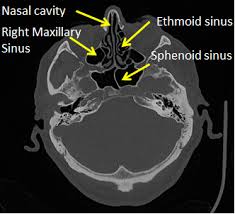

C – Cribiform plate (keros classification) – to assess the depth of olfactory fossa, length of lateral lamella, symmetry, slope or any dehiscence.

L – Lamina Papyracea – look for dehiscence, so if there is dehiscence make sure to be extra careful when using microdebrider around this area as incident such as injuring the orbital fat or rectus muscle could occur.

O – Onodi cell – if present, to assess its relationship to optic nerve, ICA, dehiscence (coronal and axial) and presence of horizontal septa.

S – Sphenoid sinus – pneumatization, septations, dehiscence of carotid artery or optic nerve.

S – Skull base – dehiscence, slope (examine sagittal plane of CT scan)

E – Ethmoidal artery position (skull base or pedicle), symmetrical? Usually anterior ethmoidal artery (~40% hanging )